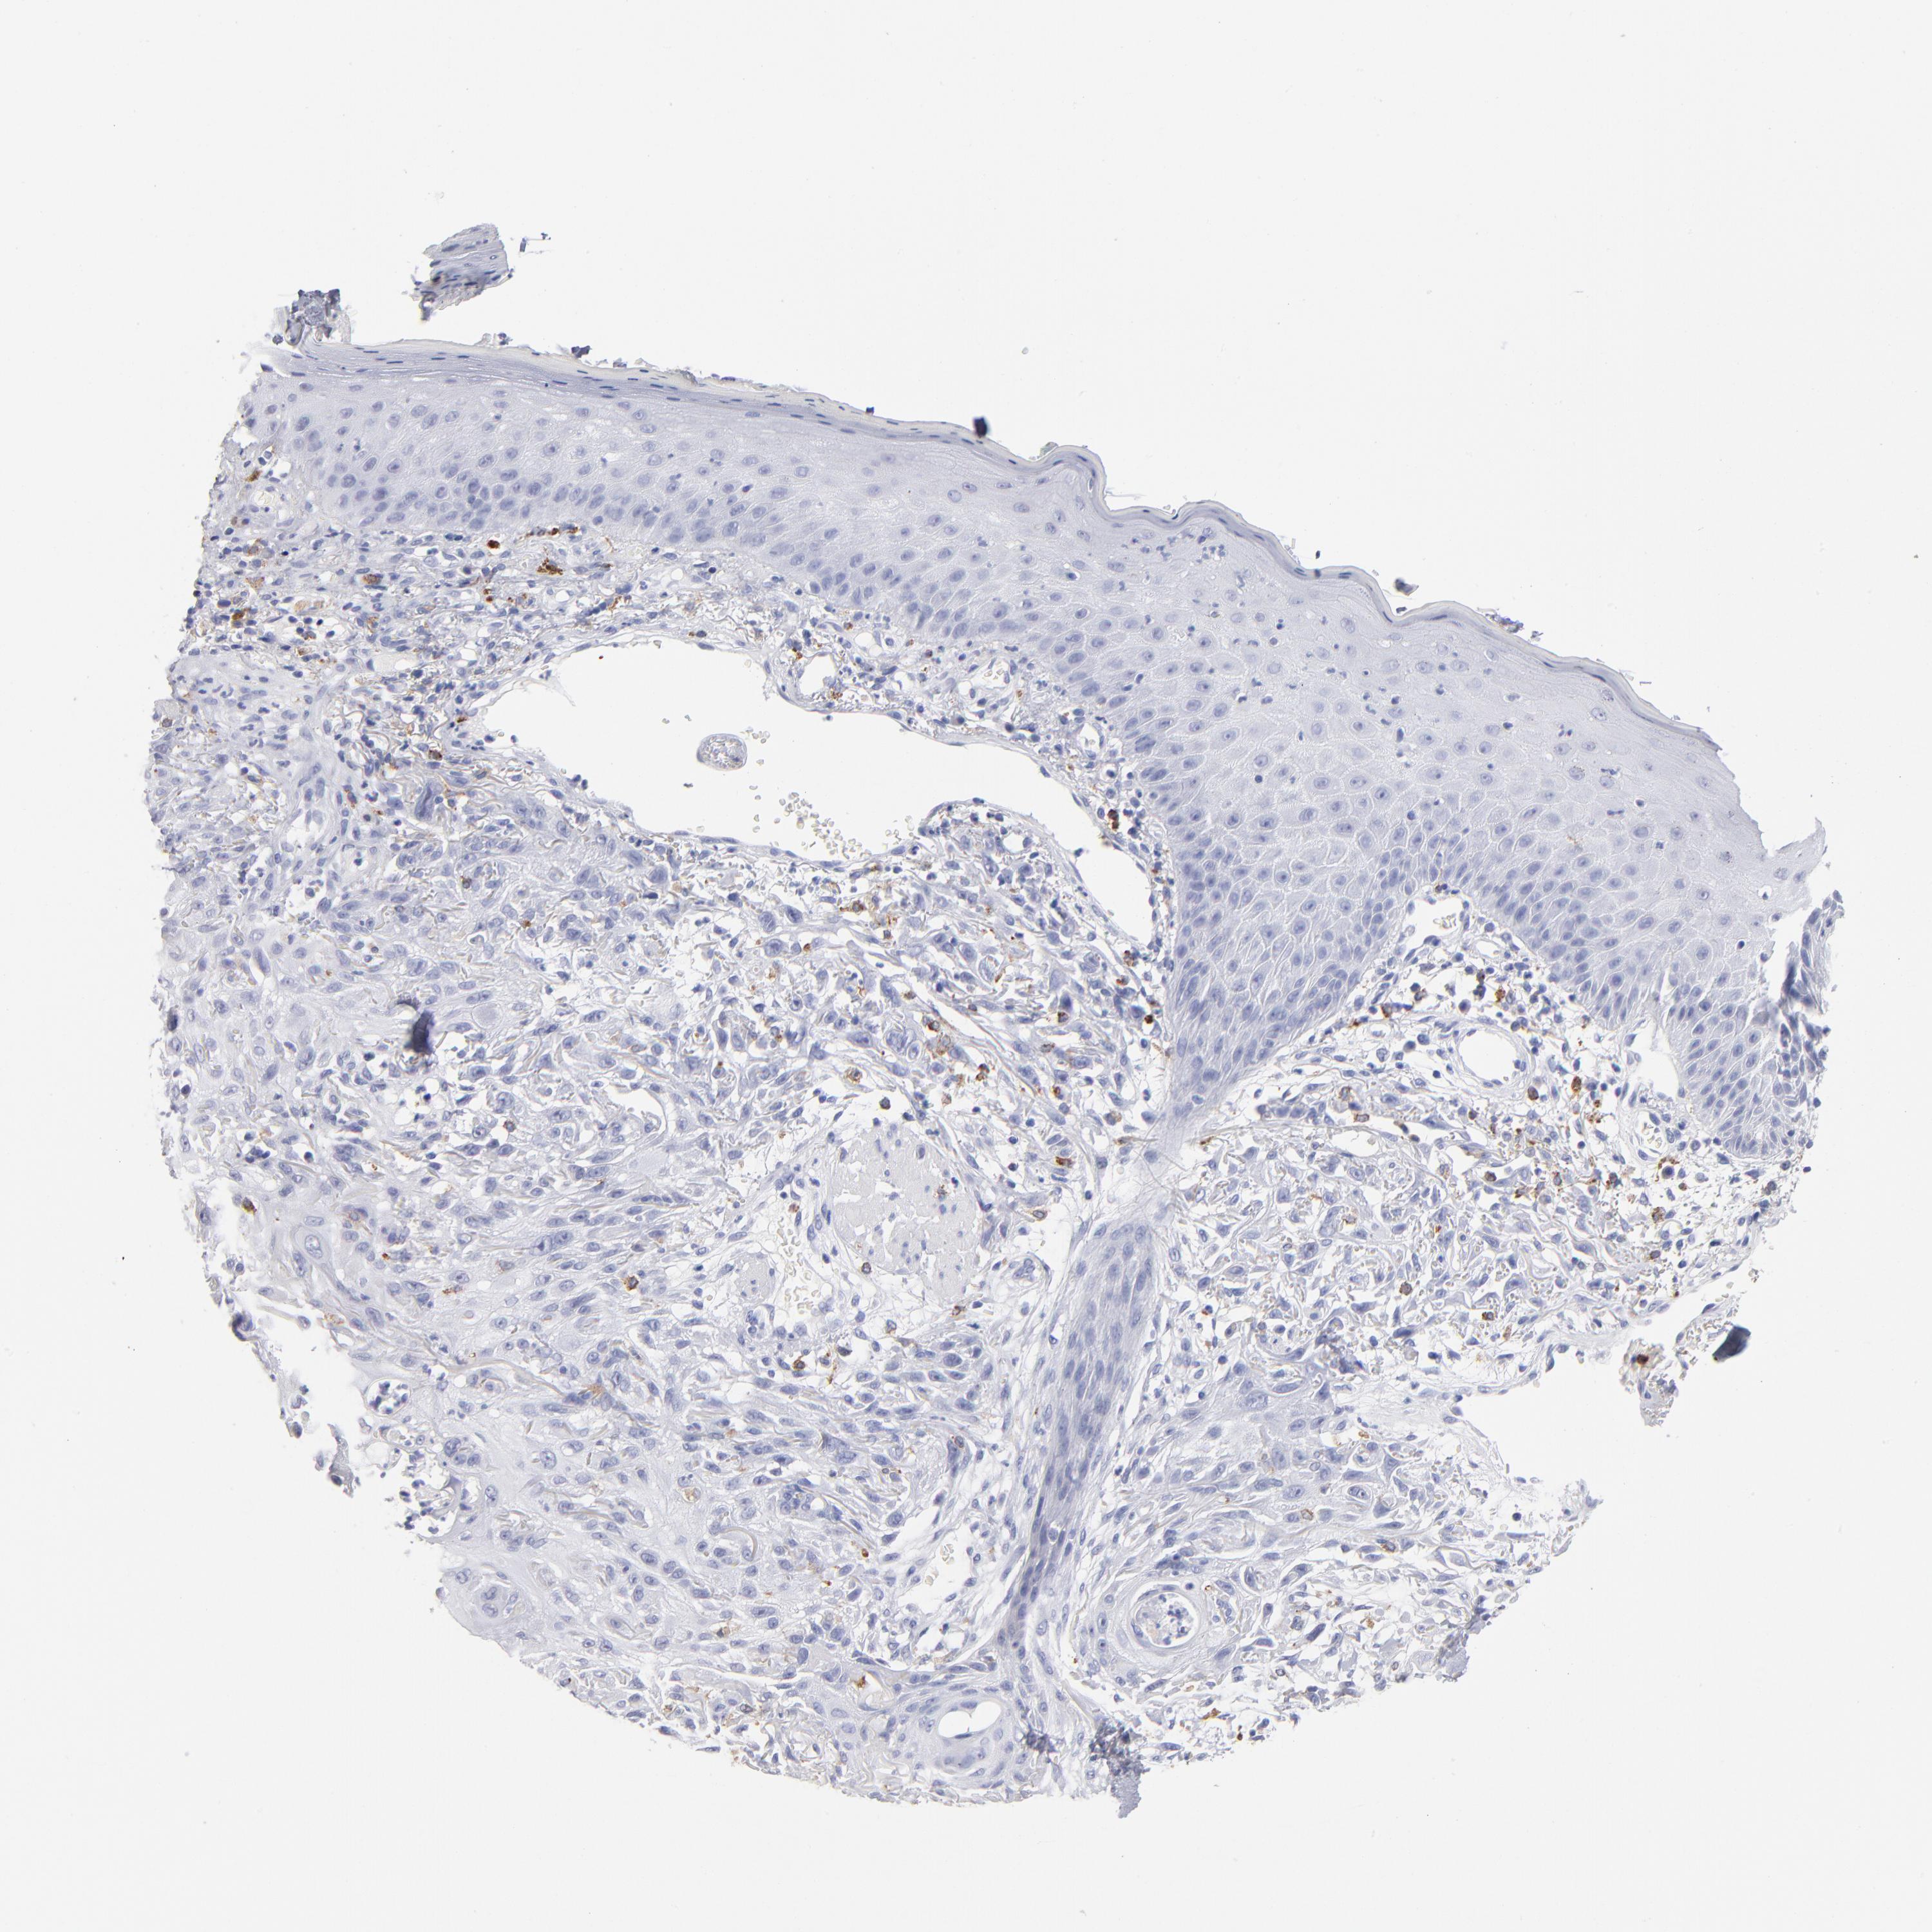

SKIN CANCER - Protein expressioni

A mouse-over function shows sample information and annotation data. Click on an image to view it in a full screen mode. Samples can be filtered based on level of antibody staining by selecting one or several of the following categories: high, medium, low and not detected. The assay and annotation is described here.

Antibody stainingi

Antibody staining in the annotated cell types in the current human tissue is reported as not detected, low, medium, or high, based on conventional immunohistochemistry profiling in selected tissues. This score is based on the combination of the staining intensity and fraction of stained cells.

Each image is clickable and will lead to virtual microscopy that enables deeper exploration of all samples and also displays staining intensity scores, fraction scores and subcellular localization as well as patient and tissue information for each sample.

Antibody HPA003740

Squamous cell carcinoma, NOS